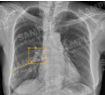

대표도면

대표도면 표

모달리티 폐암 영상데이터 데이터 포맷 어노테이션 항목 메타데이터 JSON 형식

X-ray 폐암 진단 의료 영상-대표도면-X-ray 예시 이미지 DICOM 단일 결절 부위

Bounding Box

체크

· DICOM 파일

· (비식별화 후)

· age, sex, machine name

· Json 파일 - 환자:json = 1:1

· Excel 파일

-양성/악성정보 비식별 환자ID, 나이, 성별, 병리결과, 흡연력

(악성의 경우만 병리결과 수집)